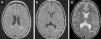

La histiocitosis de células de Langerhans (HCL) es una enfermedad rara caracterizada por la acumulación en los tejidos de células dendríticas anómalas similares a las células de Langerhans. La presentación clínica varía desde la aparición de una lesión ósea única hasta la afectación multisistémica. La implicación del sistema nervioso central (SNC), manifestada como diabetes insípida secundaria a afectación hipofisaria, es conocida desde la descripción original de la enfermedad. En la actualidad, se diferencian 2 tipos de lesiones del SNC: las lesiones seudotumorales, con infiltración por las células de Langerhans, cuya manifestación más frecuente es la infiltración hipofisaria, y otras, de más reciente descripción, las lesiones neurodegenerativas del SNC, asociadas a deterioro neurológico, que constituyen una complicación de la enfermedad de causa discutida. Nuestro objetivo es describir las manifestaciones radiológicas de la HCL en el SNC en los pacientes pediátricos.

Langerhans cell histiocytosis (LCH) is a rare disease characterized by the accumulation within tissues of anomalous dendritic cells similar to Langerhans cells. The clinical presentation varies, ranging from the appearance of a single bone lesion to multisystemic involvement. Central nervous system (CNS) involvement, manifesting as diabetes insipidus secondary to pituitary involvement, has been known since the original description of the disease. Two types of CNS lesions are currently differentiated. The first, pseudotumoral lesions with infiltration by Langerhans cells, most commonly manifests as pituitary infiltration. The second, described more recently, consists of neurodegenerative lesions of the CNS associated with neurologic deterioration. This second type of lesion constitutes a complication of the disease; however, there is no consensus about the cause of this complication. Our objective was to describe the radiologic manifestations of LCH in the CNS in pediatric patients.